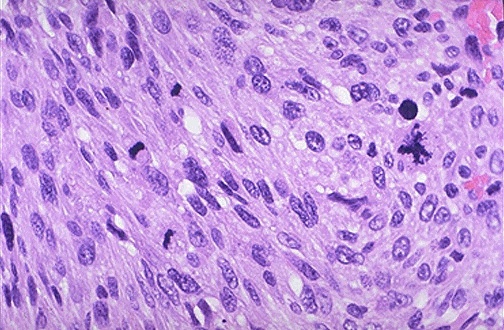

Mitotic activity in sarcoma

Abnormal mitotic feature observed

Numerous mitoses

Very large abnormal mitotic figure

Immunohistochemical marker for sarcoma

Contrast between sarcoma cells and muscle fibers

Vimentin

Stained = sarcoma